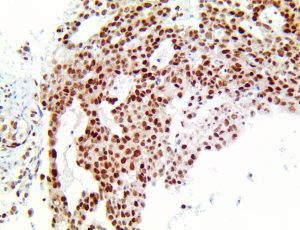

It is the ICU physician who is most likely to witness one of the deadliest manifestations of the abnormal immunological response, the cytokine storm syndrome (CSS). This response is also referred to by some as the cytokine release syndrome (CRS). CSS is characterized by continuous activation and expansion of macrophage and lymphocyte populations, which secrete large amounts of cytokines, causing the cytokine storm. This massive cytokine release is akin to hemophagocytic lymphohistiocytosis (HLH) disease, a syndrome characterized by initial unchecked and persistent activation of cytotoxic T lymphocytes and NK cells.

Clinical and laboratory manifestations of HLH include fever, enlarged liver and/or spleen, neurologic dysfunction, coagulopathy, liver dysfunction, cytopenias (i.e., low levels of erythrocytes, leukocytes, and/or platelets), hypertriglyceridemia, hyperferritinemia, hemophagocytosis, and eventually diminished NK cell activity as the immune system becomes progressively paralyzed. HLH can be familial (primary HLH) or secondary to another disease process (sHLH), such as rheumatic disease, in which it is referred to as macrophage activation syndrome (MAS, characterized by elevated ferritin).